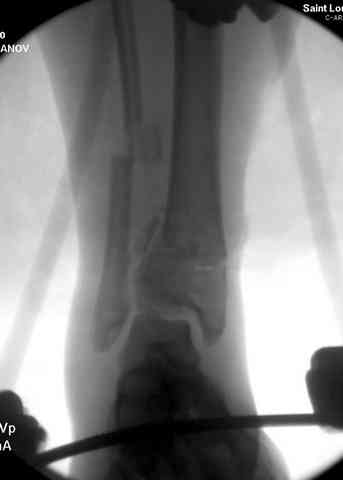

Яков изложил все необходимые аспекты лечения переломов пилона, и, не желая менять тему, решил выставить нашу точку зрения в двух клинических примерах.

При лечении внутрисуставных переломов типа "Pilon"

или "Tibial Plateau" на голени, применение простых

наружных фиксаторов типа "Spanning ExFix" или "Travelling ExFix" стал одним из стандартом этапного лечения.

Здесь выставлена пара случаев перелома пилона, оба

случая леченные этапным наружным фиксатором.

Второй случай фиксирован аппаратом Илизарова.